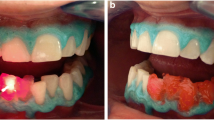

When data sets for all four channels were assessed, the greatest changes occurred in the blue channel, followed by the green channel, with luminosity and red channel data showing similar lesser changes. This corresponded to the samples appearing at the macroscopic level less brown and lighter in colour (Fig. 1).

Sequential images of the same root portion (half slice) treated with either the KTP laser with Smartbleach® gel (upper series) or the 3LT LED lamp and Smartbleach® 3LT gel (lower series). There is a clear improvement from the treatment, followed by slight relapse. From left to right, the images show the root slice at, baseline, immediately after treatment, at 1 week and after 1 month

In terms of relapse, the samples treated with the KTP laser and Smartbleach® showed a small change over 1 month by visual examination (Fig. 1), with the greatest change again being in the blue channel (p < 0.001). The extent of change was less from 1 week to 1 month than from immediately postoperatively to 1 week (p < 0.05). In contrast, those treated with the LED lamp and 3LT gel showed most change between 1 week and 1 month (p < 0.01). Overall, more relapse was seen with the samples treated with the KTP laser than with the LED, but nevertheless they remained lighter than those treated with the LED system.